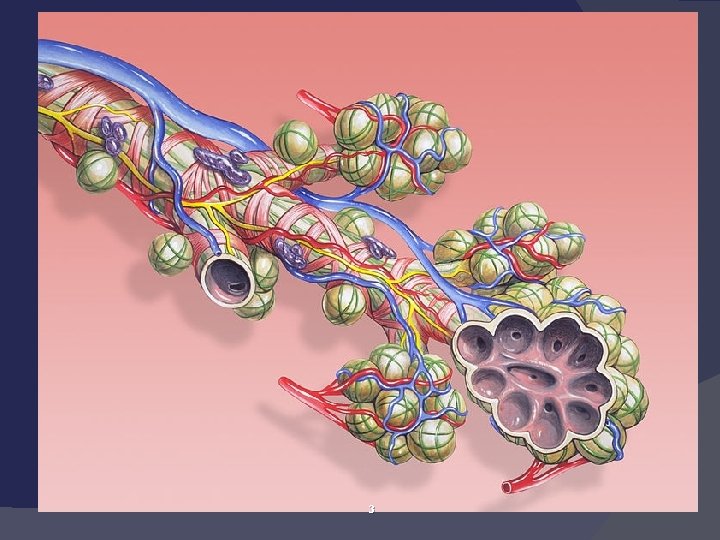

ПНЕВМОНИЯ Острое инфекционное заболевание, преимущественно бактериальной этиологии, характеризующееся очаговым (локальным)поражением респираторных отделов легких, наличием альвеолярной экссудации и выражеными в различной степени лихорадкой и интоксикацией.

Клиническая картина Интоксикационый синдром Бронхитический синдром Синдром поражения легочной паренхимы